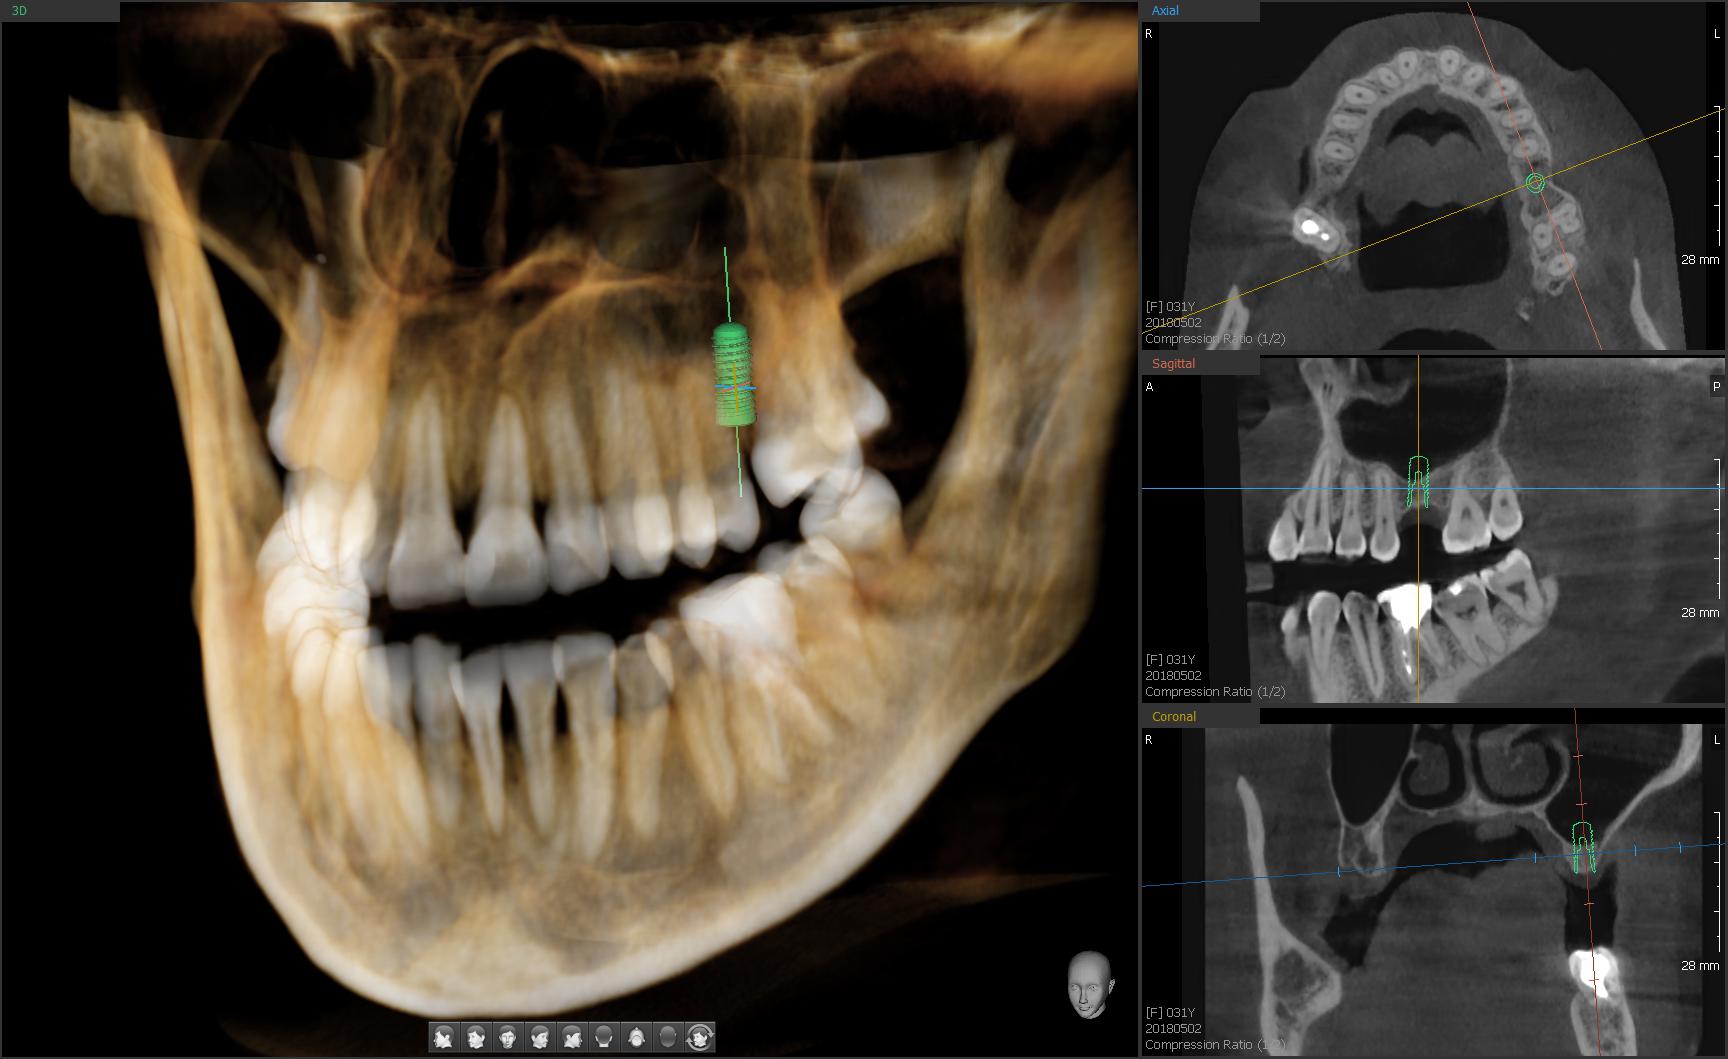

Навигационная имплантология

Применение хирургических шаблонов – это новый виток в развитии технологии имплантации зубов. Прежде всего, хирургические шаблоны нужны хирургам для точной установки имплантата. Они позволяют добиться такой точности, которой сложно достичь, даже имея богатый многолетний опыт. С помощью шаблонов можно выполнять операции на принципиально новом уровне. Их использование значительно снижает вероятность осложнений, как в момент имплантации, так и на ортопедическом этапе.